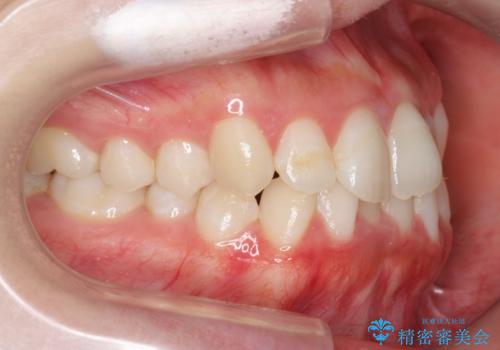

下の歯のがたつき 上より気になる

- 前歯のがたつきが気になって来院。

下の歯のがたつきが上よりも多い状態でした。

前歯のがたつきもしっかり治り、喜んでいただけました。